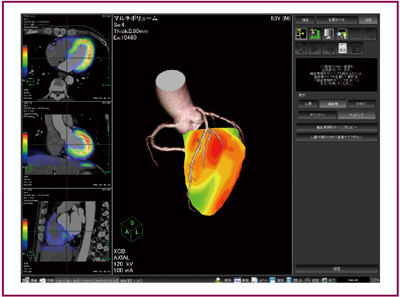

●CTコロナリー画像と心筋シンチグラフィ画像の3Dフュージョン

循環器領域では,前述のCTを利用した冠状動脈の形状診断と合わせて,RI心筋シンチグラフィ画像を用いた心筋虚血評価も行われる。AZE VirtualPlaceでは,先進的な画像位置合わせアルゴリズム(アトラス法)を用いて,CT画像とRI画像の自動位置合わせを行うことができる(図3)。従来の位置合わせアルゴリズムでは,CTの高い解像度の画像とRI画像の間の共通点を見つけることが難しく,その結果,好ましい位置合わせ結果を得ることができなかった。これを解決するために,新しいアルゴリズム(アトラス法)では,CT画像とRI画像の双方の間に平均的な情報(アトラスデータ)を用い,CT,RIのデータをそれぞれアトラスデータに近づけることにより,位置合わせの精度を格段に向上させることに成功した。このアルゴリズムを使用して位置合わせを行った画像を,CT冠状動脈解析のコロナリー画像と重ね合わせることで,虚血の広がりとその責任血管の位置関係を容易かつ正確に認識することが可能となった。

図3 CTコロナリーと心筋シンチグラフィのフュージョン